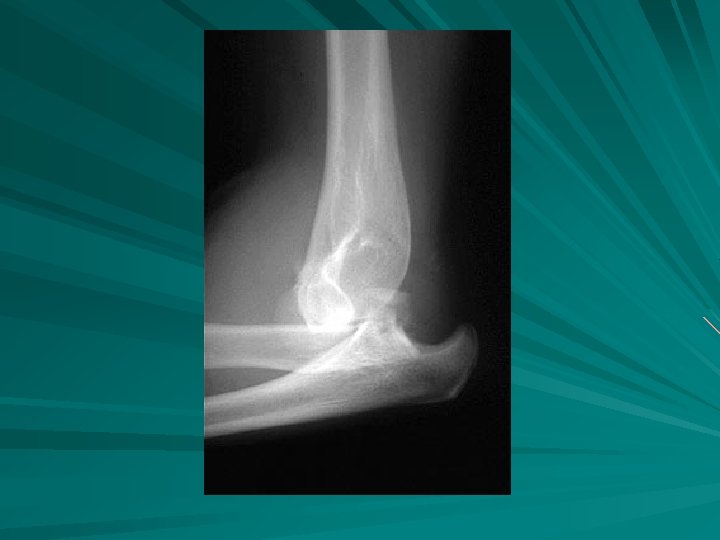

FX RADIAL HEAD